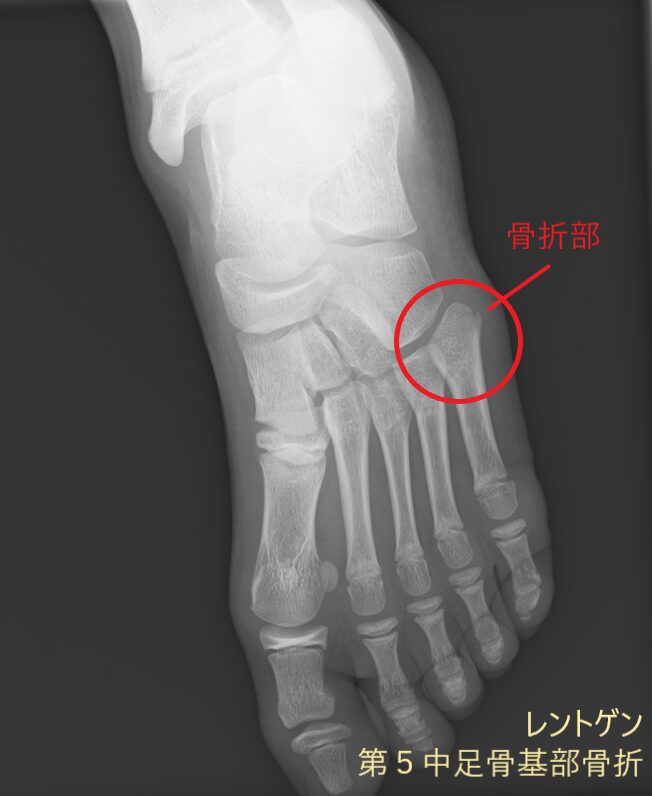

レントゲン画像には映りにくい筋肉や腱、靭帯などの状態に加え、骨の様子もあわせて確認できます。